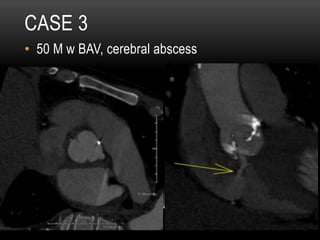

CASE 3

•  50 M w hx BAV, cerebral abscess, new heart

failure

•  50 M w BAV, cerebral abscess

INFECTIOUS ENDOCARDITIS (IE) WITH

SUBVALVULAR ABSCESS AND AORTO-RIGHT

ATRIAL FISTULA

•  HACEK endocarditis